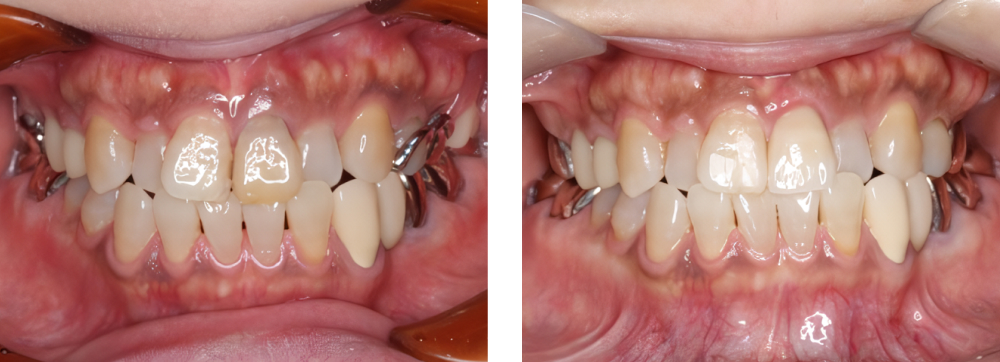

小児矯正

術前

術後

| 治療内容 | 叢生に対して床矯正を使用し治療を行った |

|---|---|

| 治療期間・回数 | 20カ月間・19回(動的治療まで) |

| 費用 ※自由診療となります |

矯正検査①:33,000円 床装置(ネジあり):77,000円 ×2 床装置(ネジなし):55,000円 ×2 |

| リスク・副作用 |

|